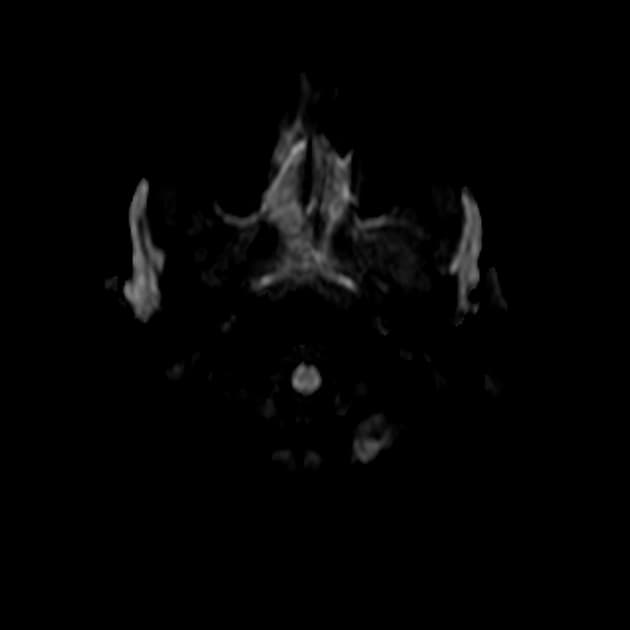

Chụp cộng hưởng từ (MRI) cho thấy các đặc điểm điển hình của bệnh xơ cứng rải rác. Ngoài ra, một số tổn thương có tín hiệu tăng trên hình ảnh T1 (T1 hyperintense).

- Các tổn thương rải rác, dạng vệt hoặc hình tròn, tăng tín hiệu trên hình ảnh khuếch tán (diffusion-weighted imaging), khu trú chủ yếu ở vùng chất trắng quanh thất (periventricular white matter), chất trắng ở bán nguyệt (juxtacortical white matter), thân gai thị – giao thoa thị giác (optic radiation – optic chiasm), và thân não (brainstem) – phù hợp với đặc điểm của xơ cứng rải rác (multiple sclerosis).

- Không có bằng chứng của phù độc tế bào (cytotoxic edema) cấp tính hay hạn chế khuếch tán (restricted diffusion) mới.

- "Việc không có hạn chế khuếch tán, xuất huyết hay ngấm thuốc viền màng não giúp phân biệt xơ cứng rải rác với các bệnh viêm hoặc nhiễm trùng khác."